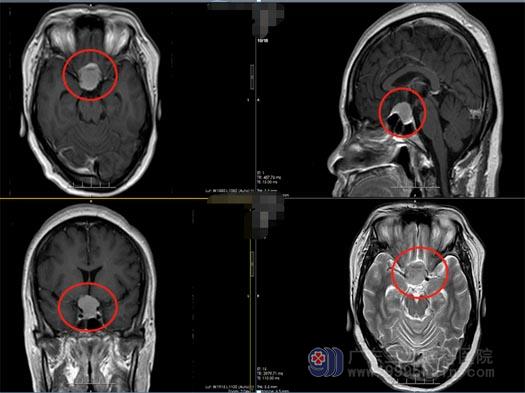

广东的陈阿姨,今年46岁。一个月前,她发现自己的右眼看东西模糊,并进行性地加重。一周前,陈阿姨的右眼彻底看不见东西了,同时伴有头痛症状,这才在家人的陪同下去当地医院做了检查,头颅MR显示鞍结节脑膜瘤。焦急的一家人寻到了广东三九脑科医院,入住神经外五科后,经过进一步的检查,陈阿姨被确诊为鞍结节脑膜瘤。

陈阿姨的症状非常典型,结合影像学检查,外五科治疗团队很快就为陈阿姨制定了手术方案。由鲁明副院长主刀,在全麻下为陈阿姨行“内镜经鼻鞍结节脑膜瘤切除术”,手术过程顺利,术后的陈阿姨恢复良好。